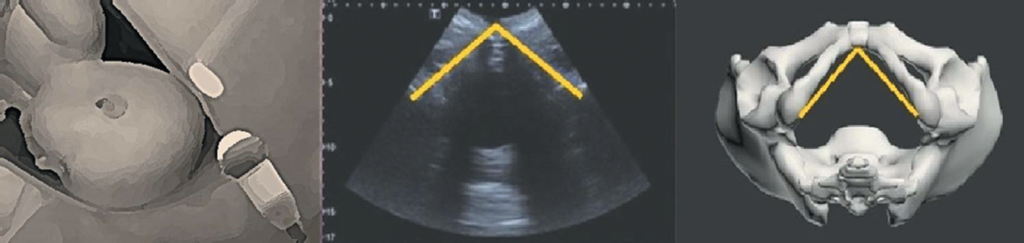

Эхографическое исследование проводили при помощи ультразвукового диагностического прибора экспертного класса Toshiba Aplio 500, сканирующего в реальном масштабе времени. Для изучения размера УЛД всем пациенткам накануне родов выполняли ультразвуковую пельвиометрию транслабиальным доступом [5, 6]. С этой целью использовали конвексный датчик с частотой преобразователя 3,5–5,0 МГц, располагающийся перпендикулярно поверхности лонного сочленения (рис. 1).

Рис. 1. Методика измерения угла лонной дуги с помощью ультразвуковой пельвиометрии

Fig. 1. Method of measuring the pubic arch angle using ultrasound pelviometry